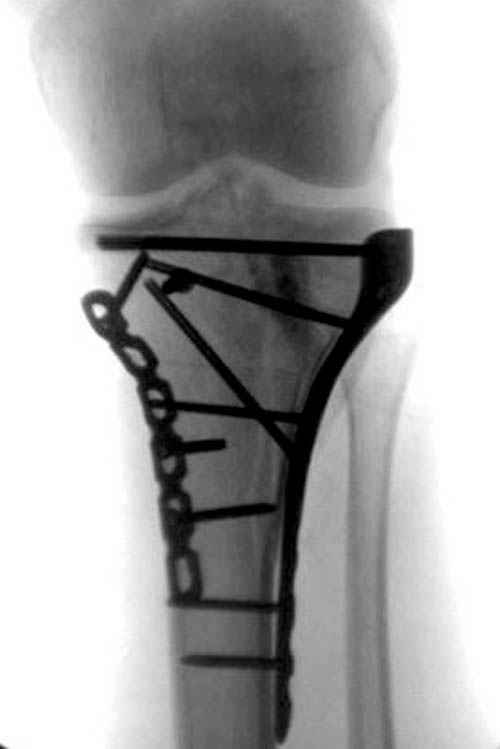

Доступ к медиальной стороне задний или медиальный, через pes или в пространстве между medial gastroc мышцы.

Надеюсь, представленные снимки разных случаев помогут разобраться в тактике, и критика примется без личной обиды.